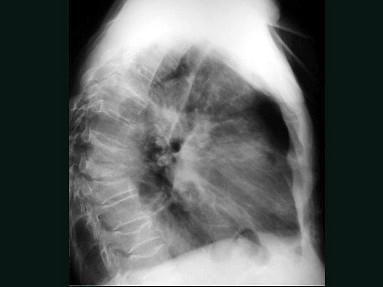

问题 男,71岁,背部酸痛,低热,乏力,消瘦2月余,结合影像学表现,最可能的诊断是?(?)

选项 A.脊柱转移瘤 B.化脓性脊柱炎 C.脊椎结核 D.椎体压缩骨折 E.阻滞椎

答案 C